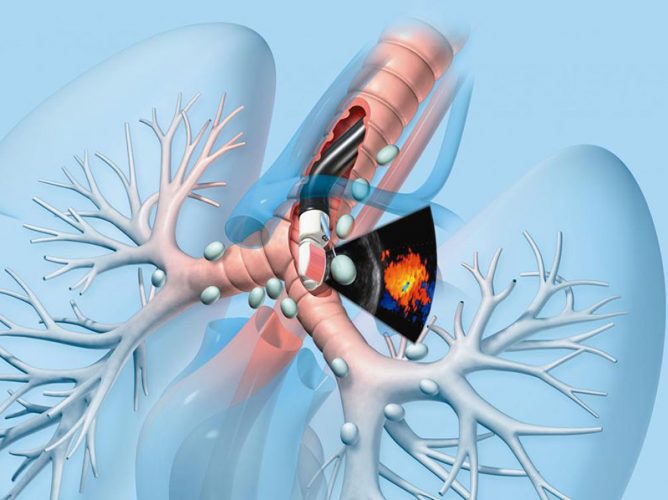

Фотографии и информация о бронхоскопии при туберкулезе